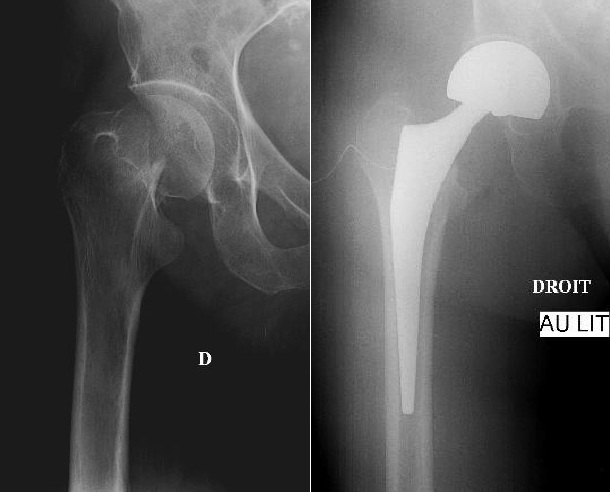

Quel est le stade Garden de cette fracture du col?

Fracture ES fémur gauche Garden 2 car pas déplacé et travées osseuses non déformées

! risque de déplacement secondaire !

Quelle prothèse a été utilisée ici?

Fracture garden 4 ES fémur traitée par

prothèse intermédiaire de hanche